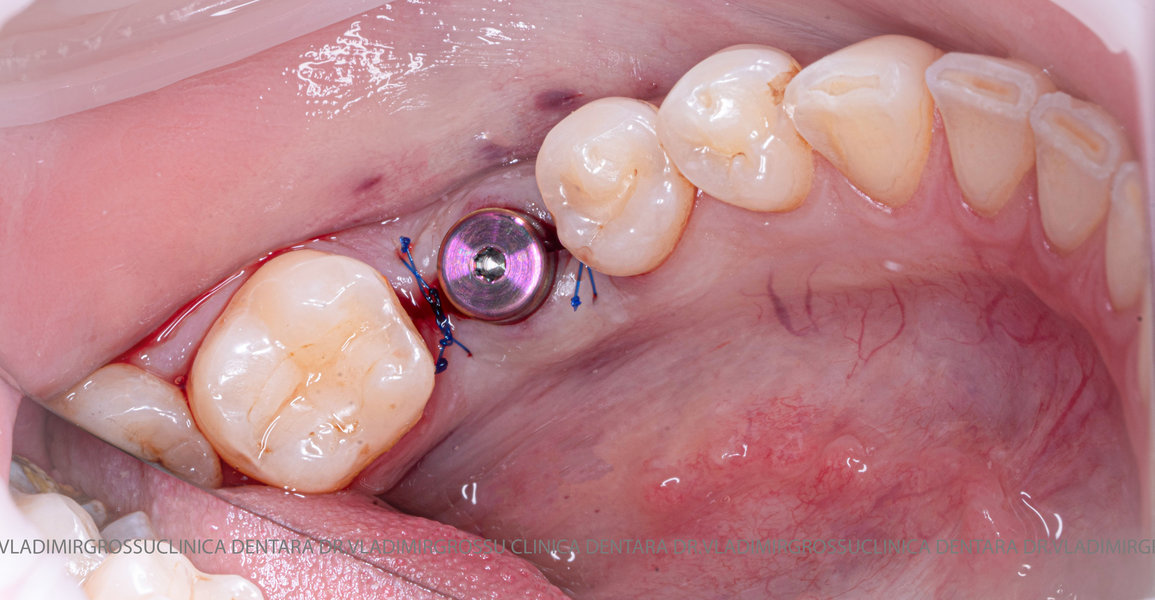

Aditia gingivală este o procedură chirurgicală ce corectează diverse probleme estetice și funcționale, cum ar fi recesiunea gingivală. În implantologia modernă, aditia de țesut moale este utilizată aproape în fiecare intervenție de inserție a implantului dentar pentru a asigura un aspect estetic natural și o bună integrare a implantului în cavitatea bucală.